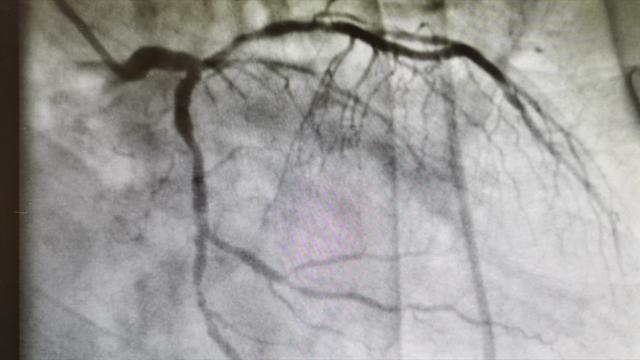

四、对哪些健康有损害?1.心脑血管疾病高发

长期熬夜,睡眠不规律的人,的确会导致心脑血管疾病高发。这已经是被医学界明确认可的事实了,尤其是脑卒中,可以说熬夜已经成为脑卒中的危险因素。高血压这类疾病,也是受睡眠调节特别明显的一类疾病,比如说血压的昼夜节律这是每个人都有的生理状态。而冠心病患者之中,很多也是因为熬夜导致的。所以,说到这里,张大夫作为一个心血管医生,强烈建议大家不要再熬夜了。